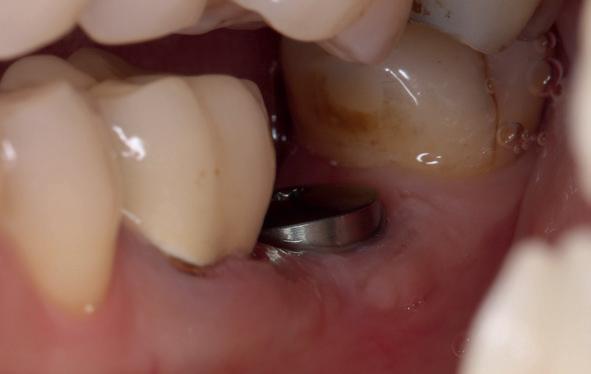

Casus

In deze casus is extractie van de 37 geïndiceerd in verband met een fistel en restpockets, zoals zichtbaar op de röntgenfoto’s (afbeelding 1). Duidelijk te zien is de forse peri-apicale ontsteking en het botverlies bij de 37, dat zowel richting buccaal als linguaal doorloopt. De 37 wordt atraumatisch verwijderd. Er is aan de linguale zijde veel bot verloren en er is sprake van een perforatie aan de buccale zijde.

Er wordt besloten om botmateriaal te plaatsen in de extractie-alveole. Vervolgens wordt het afgesloten met een titanium versterkt d-PTFE membraan (afbeelding 2). Na vier weken wordt het membraan verwijderd.

Zes maanden na extractie wordt het implantaat 37 geplaatst. Er is sprake van een goede genezing en de processushoogte en -breedte zijn behouden en opgebouwd. Ook is er zichtbaar gekeratiniseerd weefsel

1 2 Ridge preservation met d-PTFE membranen 35

gewonnen. De wond kan na het plaatsen van een healing abutment primair gesloten worden (Afbeelding 3a-3d).

In afbeeldingen 4a-c is het resultaat drie maanden na het plaatsen van het implantaat te zien. De genezing is volledig en de verwijzer kan de suprastructuur vervaardigen (afbeelding 4a-4c).

In afbeeldingen 5a-d is de implantaatkroon 37 te zien, twee jaar na plaatsing. Op de röntgenfoto is herstel van zowel corticaal als spongieus bot te zien. (De CB-CT was vervaardigd in verband met implantologische indicatie in het naastliggende gebied).

Deze casus illustreert dat er op een voorspelbare manier een ridge preservation procedure uitgevoerd kan worden met een d-PTFE membraan en er daarna voorspelbaar geïmplanteerd kan worden.